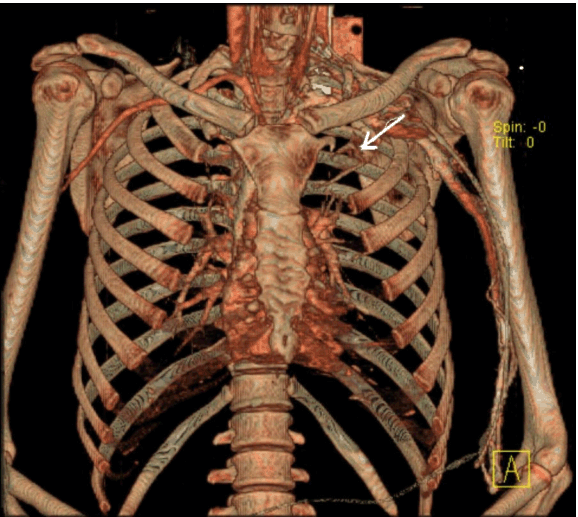

A 26-year-old left-handed healthy man presented with a three month history of repeated bilateral chest pain. Six months previously, he started heavy muscular activity of upper limbs (work out at a gym). Two months before he had been examined by his pulmonologist because chest X-ray revealed bilateral small effusion and tuberculin test had been positive. The patient started treatment as suspected tuberculous pleuritis and beside antituberculous drugs he used corticoids too. Despite treatment, difficulties remained and the patient was remitted to our clinic. On examination, there was no edema of the left arm, only prominent superficial veins on arm and left part of chest. On auscultation of the lungs, breath sounds were weakened bilaterally. Chest radiography revealed small pleural effusion. Electrocardiography and echocardiography were normal. Suspected pulmonary embolism was confirmed by computed tomography. DVT in lower limb was excluded by compression ultrasonography. Because the patient had prominent superficial veins on arm and left part of chest, we suspected left subclavian vein thrombosis, which was established by venography (Figure 1). Aortography revealed aneurysm of left subclavian artery (Figure 2) and also confirmed left thoracic outlet syndrome due to adherent first and second ribs (Figure 3), interruption of flow in left subclavian artery in abduction of left upper limb and appropriate flow in left subclavian artery in adduction of left upper limb (Figure 4). Patient was administered low molecular weight heparin as initial step, followed by the acenocoumarol therapy. A thrombophilia screen revealed prothrombin 20210A mutation, which was detected by polymerase chain reaction.

Figure 1: Venography of left upper extremity: Subclavian vein thrombosis marked by the arrow.